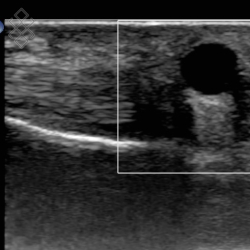

Échographie de la Main

La durée de l'examen est d'environ 20 minutes. Il est indolore et est réalisé par un médecin radiologue.